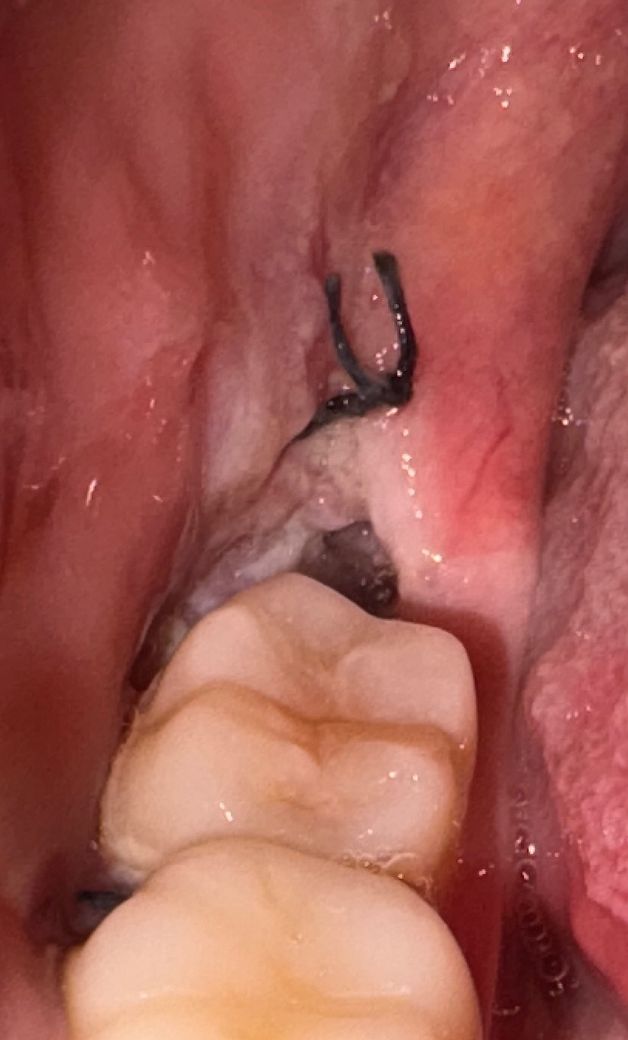

사랑니 발치 약 52시간 경과 혈병 상태

금요일 오후 3시30분경에 우측 아랫니 수평매복사랑니 발치했고 당일에 얼음찜질 열심히 해서 부기가 빠졌습니다. 다음날(토요일) 부터는 통증은 거의 없고 약간 불편한 느낌만 있는데 발치부위 사진을 찍어보니까 이렇게 어두운 회색~갈색~검은색 상태에 주변이 하얗게 되었더라고요. 잘 아물고 있는 거 맞을까요?

현재 시간으로 보았을 때 정상적인 회복 과정으로 보입니다. 주변 잇몸 색과 비교했을 때 정상적인 회복 패턴으로 판단되어 지며 일주일 뒤에 실밥을 제거하면 되겠습니다. 만약에 문제점이 있다면 통증이 극심하게 나타나고 붓기가 잘 가라앉지 않습니다.

사진으로 봤을 땐 크게 문제가 없이 잘 아물고 있는 것으로 보입니다. 사랑니를 발치했다면 발치한 부위를 자극하지 않는 것이 좋습니다. 발치한 부위를 자극하게 되면 출혈이 되고 치유가 늦어질 수 있기 때문입니다.

사진상 특별히 치유에 문제가 있는 상태는 아닌것으로 보입니다 발치 후 주의사항 잘 지키시고 약 복용 잘하시기 바랍니다

사진상으로 보면 잇몸이 잘아물고 잇는거 같습니다. 음식물이 잘 낄수 잇으니 물로 여러번 헹궈주시는게 중요합니다.